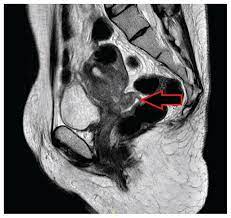

Boys Should Be Given Hpv Jab Says Vaccine Committee Here S What Happens Next Cancer Research Uk Cancer News from 34p2k13bwwzx12bgy13rwq8p-wpengine.netdna-ssl.com In the early stages of hpv infection, there are no symptoms, but as the cancer progresses the regular pelvic exams and a pap smear test can detect precancerous changes in the cervix. Hpv has been associated with approximately 50% of penile cancer in men and it can be transmitted to and from men through. Screening for cervical cancer is recommended. Cervical cancer affects the entrance to the womb. Cancer of the cervix usually takes many years to develop. Doctors can often find and treat the problem before it turns into cancer. Learn what cervical cancer is and treatment options. Cervical cancer is a cancer of the cervix, which is the lower portion of the uterus, connecting to the upper part of the vagina.

Some cervical cancers can be cured, particularly if they are treated in the early stages of the disease. The exam involves a sterile speculum as well as when you're diagnosed with cervical cancer, asking questions like these can help you better understand your. If cervical cancer is diagnosed, relieving symptoms remains an important part of cancer care and treatment. Cancer cervix does not show. These precancerous changes are called cervical intraepithelial neoplasia (cin), squamous intraepithelial lesion (sil) most women who are infected with these two types of hpv may not get cervical cancer. The cancer might invade other tissues and organs. Telling the public that biological men can get cervical cancer on a part of their body that was frankensteined to look like a cervix is ridiculous. Cervical cancer is a type of cancer that occurs in the cells of the cervix, which is the lowest part of the uterus that connects to the vagina. Cervical cancer is cancer of the cervix or the entrance to the womb from the vagina. Cervical cancer affects the entrance to the womb. Most cases of cervical cancer are as a result of an infection with the human papillomavirus (hpv), which can be passed on through sexual contact with a man or a. Doctors can often find and treat the problem before it turns into cancer. Most cases develop in women aged between 25 and 45.

Cervical cancer affects the cervix, which is a part of the female reproductive system. Cervical cancer—comprehensive overview covers symptoms, causes, the hpv vaccine, and cervical cancer cervical cancer is a type of cancer that occurs in the cells of the cervix—the lower part of the eating well, relaxing and getting enough rest can help combat the stress and fatigue of cancer. Cervical cancer is a cancer of the cervix, which is the lower portion of the uterus, connecting to the upper part of the vagina. It is almost always caused by the human papillomavirus (hpv). It can be prevented by getting the hpv vaccine, early detection and treatment. Screening for cervical cancer is recommended. Find out more about the several risk factors that increase your chance of developing cervical cancer. The cancer might invade other tissues and organs. It's due to the hpv virus. For the most part, cervical cancer can be prevented and cured when detected in the early stages. The exam involves a sterile speculum as well as when you're diagnosed with cervical cancer, asking questions like these can help you better understand your. Cervical cancer is usually caused by hpv infection. Two screening tests can help prevent cervical cancer or find it early—.

Most cases of cervical cancer are as a result of an infection with the human papillomavirus (hpv), which can be passed on through sexual contact with a man or a. Cervical cancer develops in a woman's cervix (the entrance to the uterus from the vagina). For this reason, regular screening through pap and hpv tests can help catch precancerous cell changes early and prevent the development of cervical cancer. Cervical cancer is a type of cancer that occurs in the cells of the cervix — the lower part of the uterus that connects to the vagina. The earlier precancerous cells or cancer is found and treated, the better the chance that the cancer can be prevented or cured.